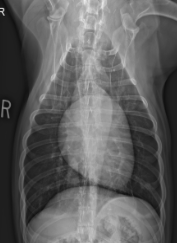

ID View

VD